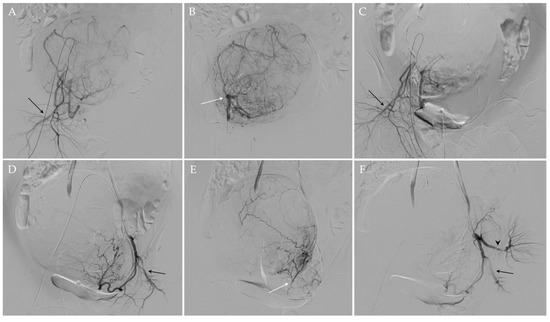

UAE procedure was performed under fluoroscopic guidance and according to the standards of practice [57,58]. In particular, after the administration of local analgesia (Lidocaine 1%), a 5 French (Fr) arterial sheath was placed in the left common femoral artery under ultrasonographic guidance. Then, internal iliac arteries were selectively catheterized using Cobra diagnostic catheter (4 or 5 Fr) (Terumo®, Tokyo, Japan) and a 0.035” angled guidewire (Terumo®, Tokyo, Japan); a subsequent diagnostic angiogram was carried out to evaluate the anatomy of uterine arteries and to confirm that no vascular anomalies are present and other organs are not affected. Subsequently, the uterine artery is selectively catheterized with a microcatheter (2.7 F) and a microwire (0.021”) (Progreat; Terumo®, Tokyo, Japan), and distal embolization was achieved using microspheres 500–700 μm or 700–900 μm in diameter (Embosphere®; Merit Medical/Biosphere, Roissy, France) or 500–710 μm nonspherical particles (Contour®; Boston Scientific, Natick, MA, USA). Once the embolization is completed on one side, the process is repeated on the opposite side in the same fashion. In the presence of a utero-ovarian anastomosis, a micro-coil was positioned in advance to protect the ovary. At the end of the procedure, a final angiogram was obtained to confirm the correct occlusion of both uterine arteries (Figure 3). The specific embolic agent and the number of particles used were at the discretion of the interventional radiologist, depending on the fibroid size, and the endpoint of the embolization procedure was complete or near complete stasis of blood flow in the uterine artery. The mean number of vials used per procedure was 3.8 (range 1–9), in agreement with the reference works [59].

Figure 3.

UAE of the same patient. Using a transfemoral approach, the preliminary angiographic study (A,D) allowed an adequate visualization of the right and left uterine arteries, which appeared hypertrophic, and the right and left pudendal arteries (black arrows in (A,D), respectively). After the superselective catheterization of the right and left uterine arteries (white arrows (B,E) respectively), embolization was performed. At the end of the procedure, the occlusion of both uterine arteries was documented and the patency of both pudendal arteries (black arrows in (C,F)) and of the left gluteal artery (black arrowhead in (F)) was appreciated.